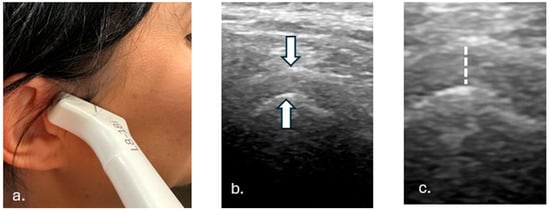

2.2. Examination Protocol

2.7. TMJ Space Width Measurement Algorithm